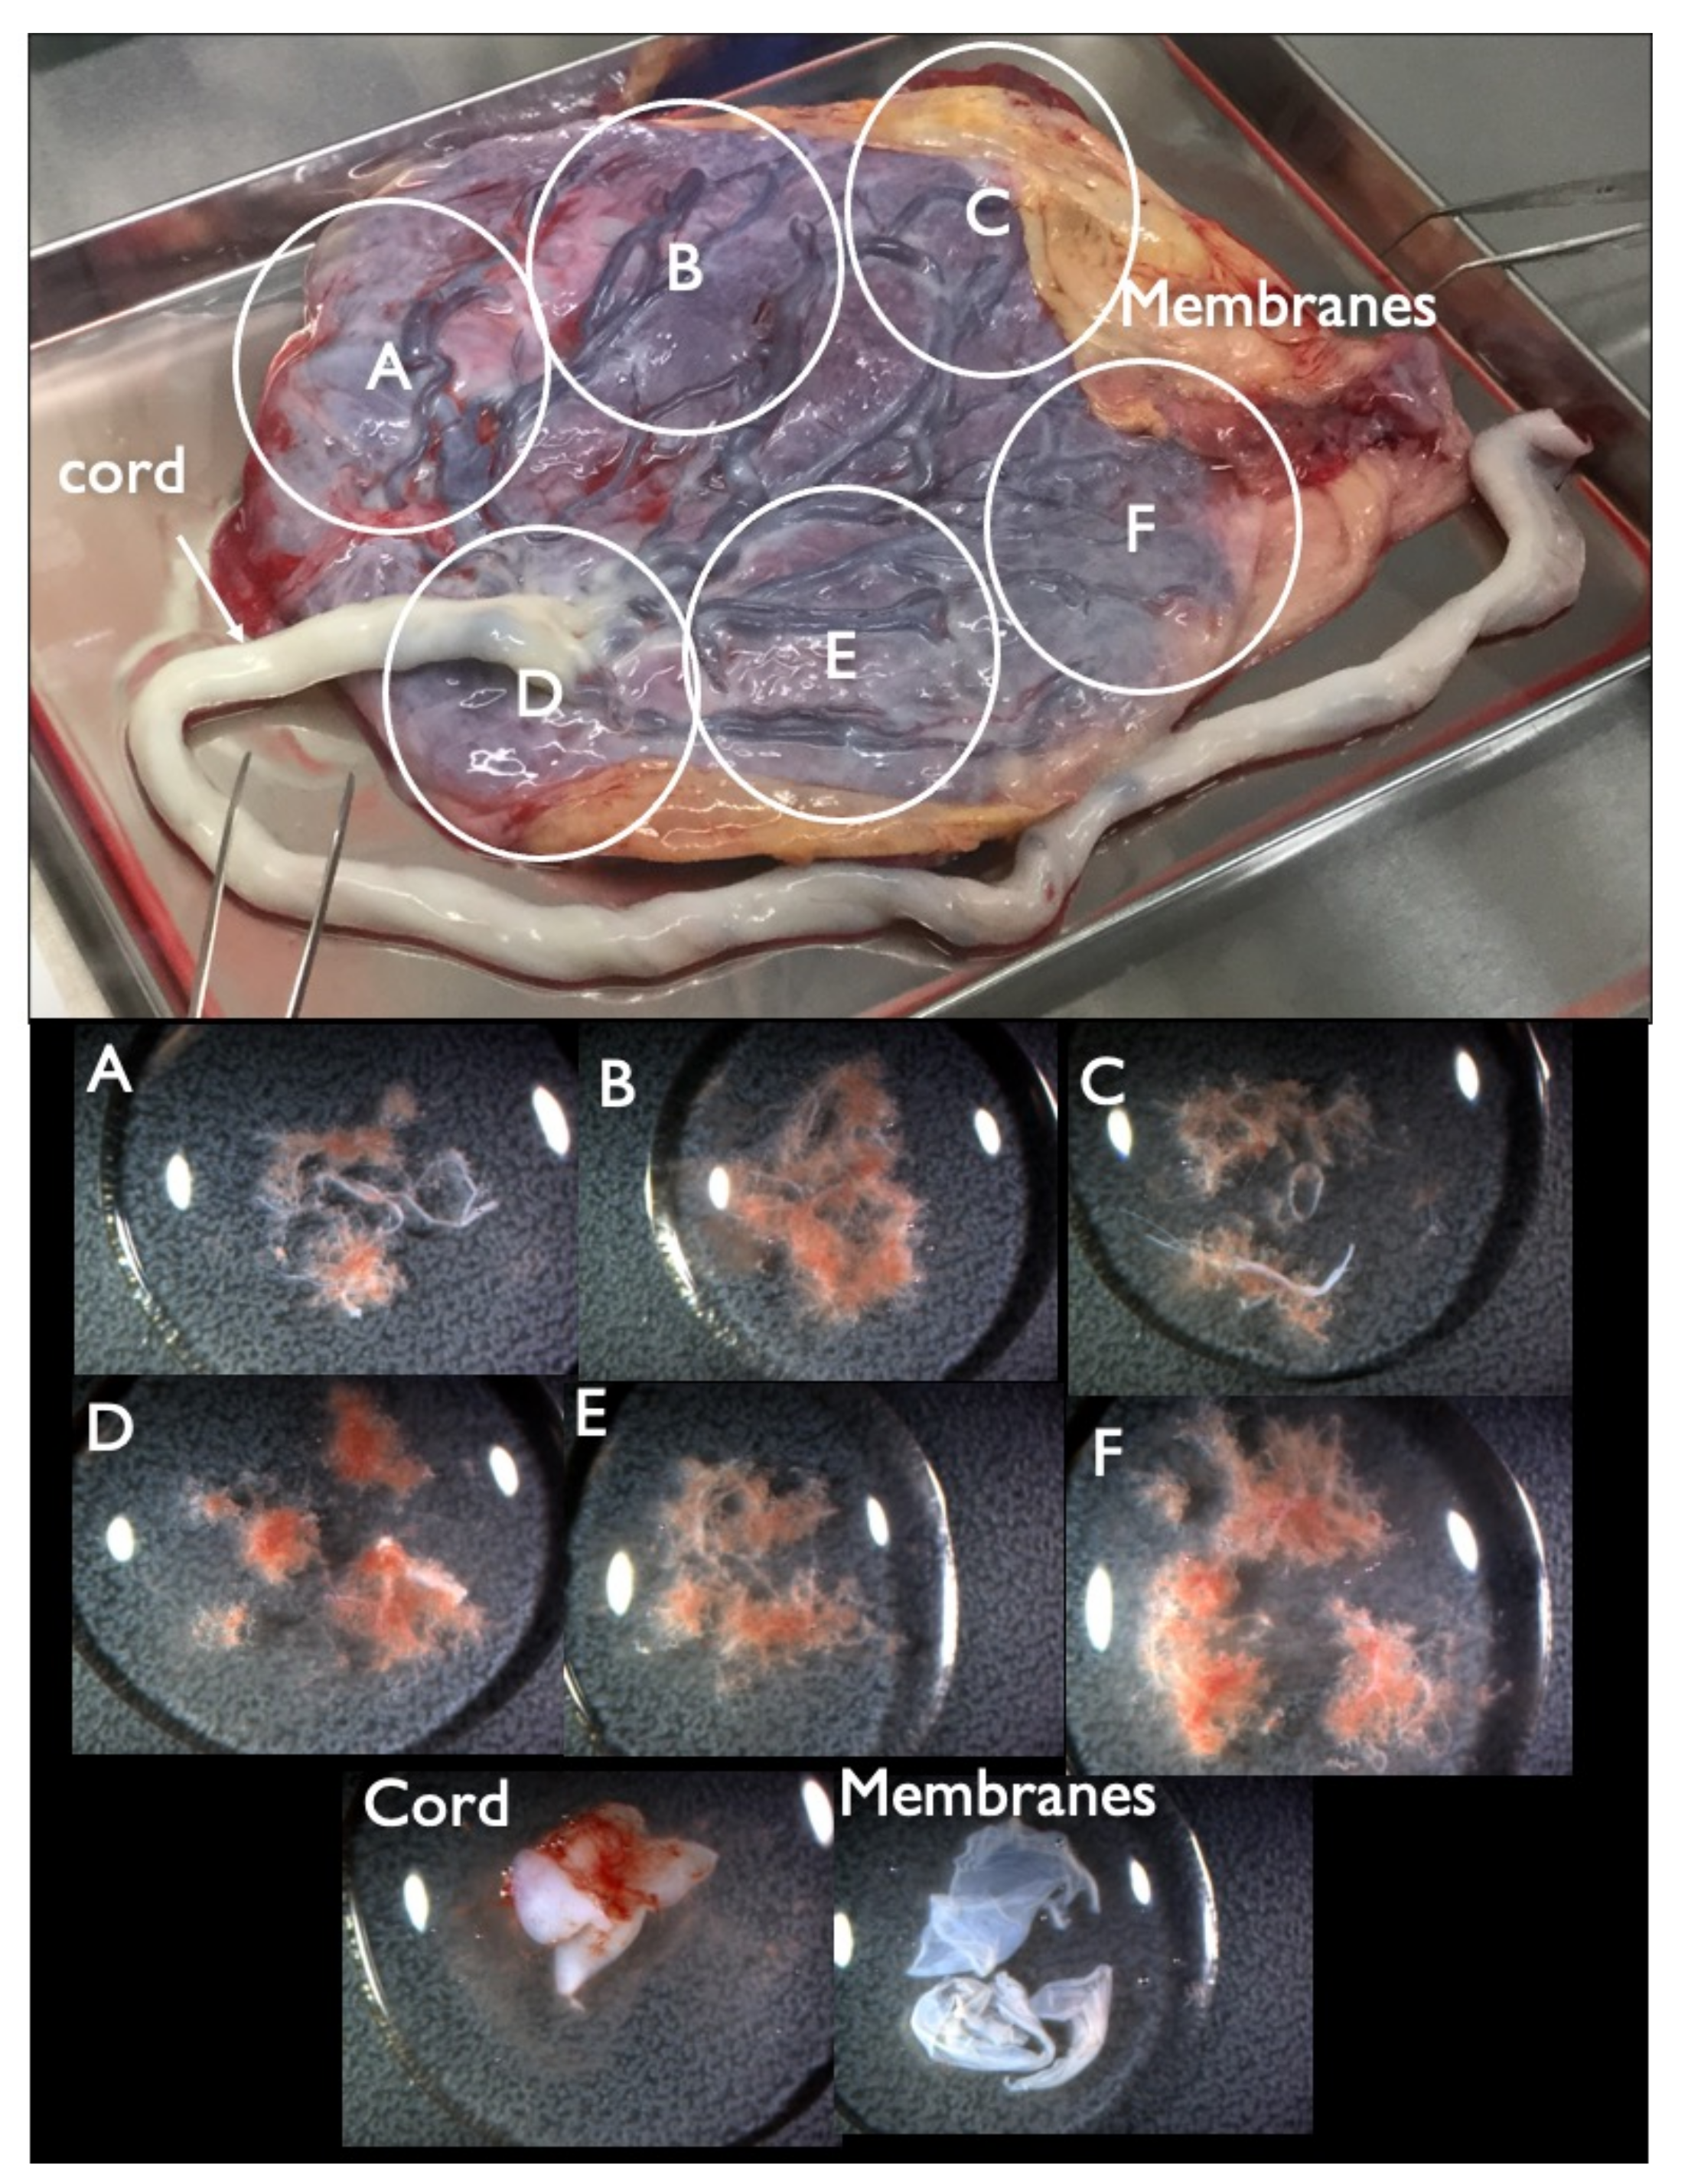

| FP1 | 45,X | T21 positive | 3.55 | MX+ T21 (16%) | MX+D21 | MX+ T21 (8%) | MX+D21 | – | – | MX+ T21 (4%) | 46,XX | CPM | + | 8.8 | Increased NT, CH, General edema, PE bilateral, Small NB, Tachycardia, Short FL/HL, Turner is strongly suspected | |

| FP3 | 46,XY | T21 positive | 7.52 | D21 | D21 | D21 | D21 | D21 | D21 | D21 | T21 (14–74%) * | 46,XX | nonviable twin with T21 | – | 1.4 | Small NB, TR mild, DCDA vanishing twin with a nonviable fetus |

| Case FP3–Specimen | FISH | G–Band | |

|---|---|---|---|

| Disomy 21 | Trisomy 21 | ||

| Placenta–A | 100% | 0% | 46,XY |

| Placenta–B | 100% | 0% | culture failure |

| Placenta–C | 100% | 0% | 46,XY |

| Placenta–D | 100% | 0% | 46,XY |

| Placenta–E | 100% | 0% | 46,XY |

| Cord | 100% | 0% | 46,XY |

| Membranes–1 | 86% | 14% | – |

| Membranes–2 | 90% | 10% | – |

| Membranes–3 | 16% | 74% | 47,XY,+21 |

| Membranes–4 | 100% | 0% | – |

| Membranes–5 | 100% | 0% | – |